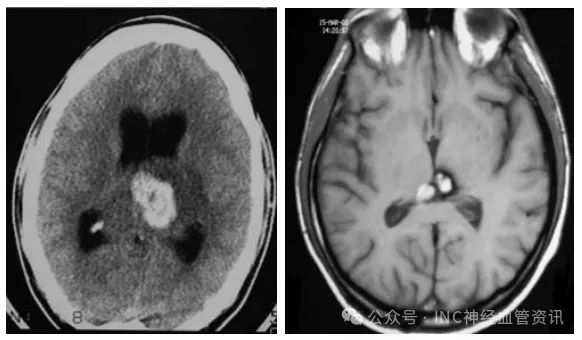

平时无任何症状的20岁女孩,怎么就突发脑干出血,偏瘫昏迷?

一说到脑瘤,绝大多数人的脑海里马上就会浮现出这样的画面:恶心呕吐,头痛不止,视力下降、走路不稳,严重甚至生活不能自理事实真的全然如此吗?当然不是! 这样回答,肯定会有人反...